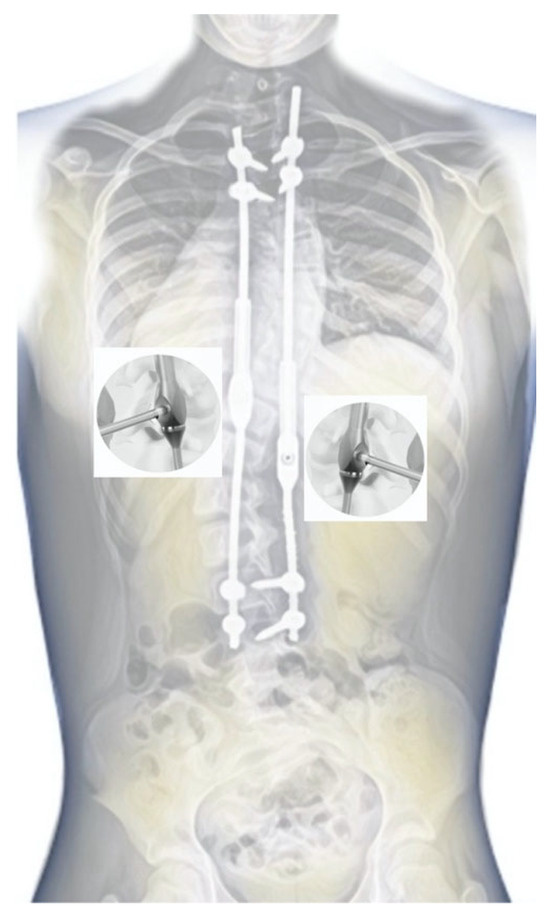

2.1. Surgical Technique